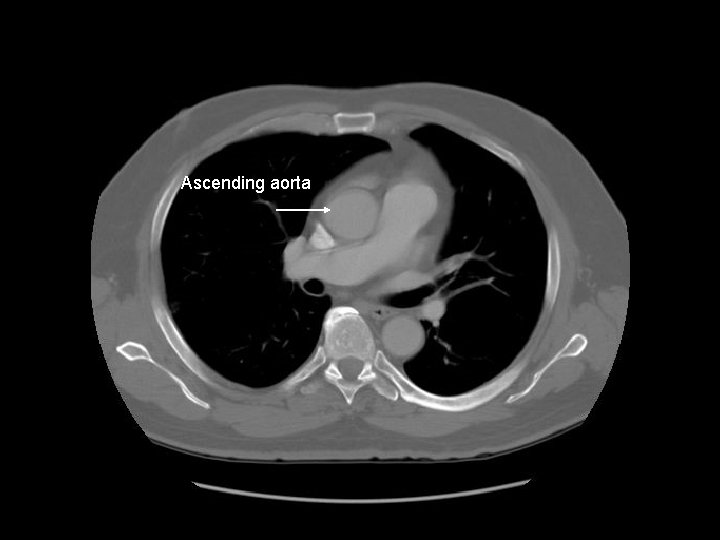

Ascending aorta Main pulmonary artery Descending aorta

Ascending aorta